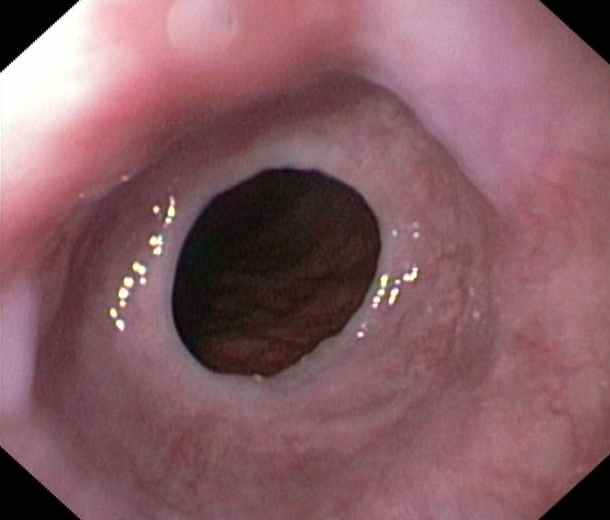

Oesophagus:

Web or ring due to chronic reflux diseases